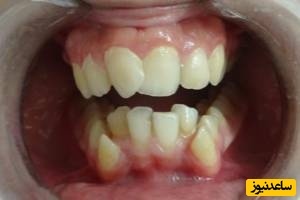

مطابق نبودن خط میدلاین دندان ها

مطابق نبودن خط میانی دندان ها زمانی ایجاد می شود که خط میانی جلویی دندان های بالا با خط میانی دندان های پایین مطابقت نداشته باشد. این وضعیت زمانی رخ می دهد که قسمت های عقبی نیش با هم تطابق نداشته باشند یا بطور مناسب روی هم قرار نگیرند که امکان دارد بر رشد فک و عملکرد صحیح دندان ها تاثیر بگذارد.